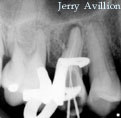

The invited case # 15 : Dr. Jerry Avillion

Our fifteenth guest is Dr. Jerry Avillion. Dr. Avillion is B.S. in Biology, Penn State University 1980. His D.D.S. is from the Medical College of Virginia, 1984, and his Certificate in Endodontics is also from the Medical College of Virginia, 1986. He actually has a private practice dedicated to Endodontics in Fort Smith, Arkansas.

Here you can enjoy several "supreme" cases performed by Dr. Avillion :

(click on the images to enlarge)